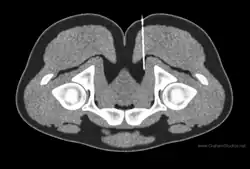

Ultrasound-guided peripheral nerve block

Ultrasound-guided peripheral nerve block is a procedure that allows real-time imaging of the positions of the targeted nerve, needle, and surrounding vasculature and other anatomical structures.[16] This visual aid increases the success rate of the block and may reduce the risk of complications.[17][18] It may also reduce the amount of local anesthetic required,[19] while reducing the onset time of blocks.[20] Ultrasound has also resulted in an exponential rise in fascial plane blocks.[21] Ultrasound is particularly well-suited for regional anesthesia, since many of the anesthesia targets (e.g., brachial plexus, femoral nerve) have large blood vessels that travel with the target nerves.[10] Direct visualization of nerves is not just important for localization, but also to ensure that the injected material surrounds the nerve. Likewise, visualization of blood vessels is important to ensure that needle placement avoids blood vessels, which often travel directly parallel to nerves.[20]

Ultrasound machine is generally portable and inexpensive in comparison to the CT scanner, fluoroscopic machine, and MRI scanner.[22] The relatively low cost of an ultrasound machine compared to other imaging machines allows for its widespread availability.[23]

Ultrasound has a few limitations. First an acoustic window is required, and certain tissue types such as bone can interfere with image acquisition.[24] Next hand-operated probe can make the images challenging for surgical planning when the exact needle location must be known.[7] CT and MRI have standard slicing orientations (sagittal, coronal, axial), but for ultrasound the orientation of the 2D image depends on the position and orientation of a probe held by the operator. Lastly ultrasound has a tradeoff between penetration depth and resolution. Higher frequencies provide better resolution but have less penetration depth. You may be able to acquire good resolution at shallow depths or see deep structures only with poor resolution. The limited penetration depth and resolution tends to make ultrasound a poor choice in particular for deeply situated pelvic nerves.[7]